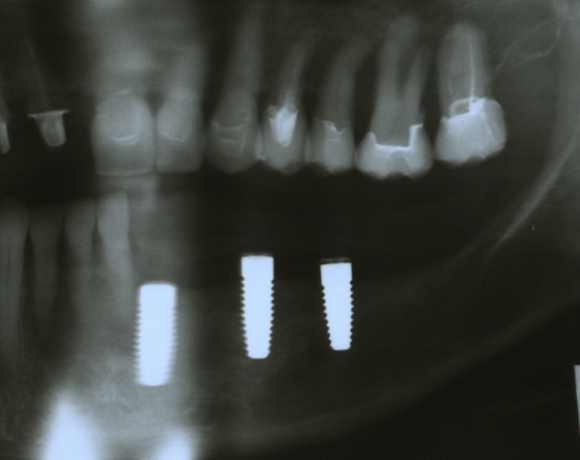

Knochenspaltung Unterkiefer 32 – 36

Die Knochenspaltung auch Bonesplitting genannt, ist eine geeignete Möglichkeit im Unterkieferseitenzahnbereich Knochen aufzubauen, um Implanate setzen zu können. Vorraussetzung ist eine ausreichende Knochenhöhe.

spaltung und drei Implantaten offen. Heute ist sie sehr zufrieden und bereut es nicht gleich diese

Lösung gewählt zu haben.